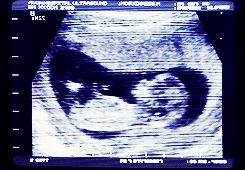

19 fontos kérdés, amit minden kismama feltesz a terhesség alatt

Az első terhesség előtt – és közben is – tele vagyunk kérdésekkel. Mindenre ráguglizunk, aztán a fórumokon olvasható sok riasztó és szomorú sztori után ezt örökre megbánjuk és megfogadjuk, ezentúl csak az orvosunktól kérdezünk. Persze van, amire ő se tudja a választ, vagy nem feltétlenül azt válaszolja, amit kéne, vagy amit hallani szeretnénk.

Ettől azonban még mindenkinek megvannak a maga kis kérdései. Ebben a cikkben azt a 19 kérdést gyűjtöttük össze, ami miatt a tapasztalataink alapján a 9 hónap alatt sok kismama forgolódik álmatlanul éjszakánként és/vagy rágódik rajta napközben.